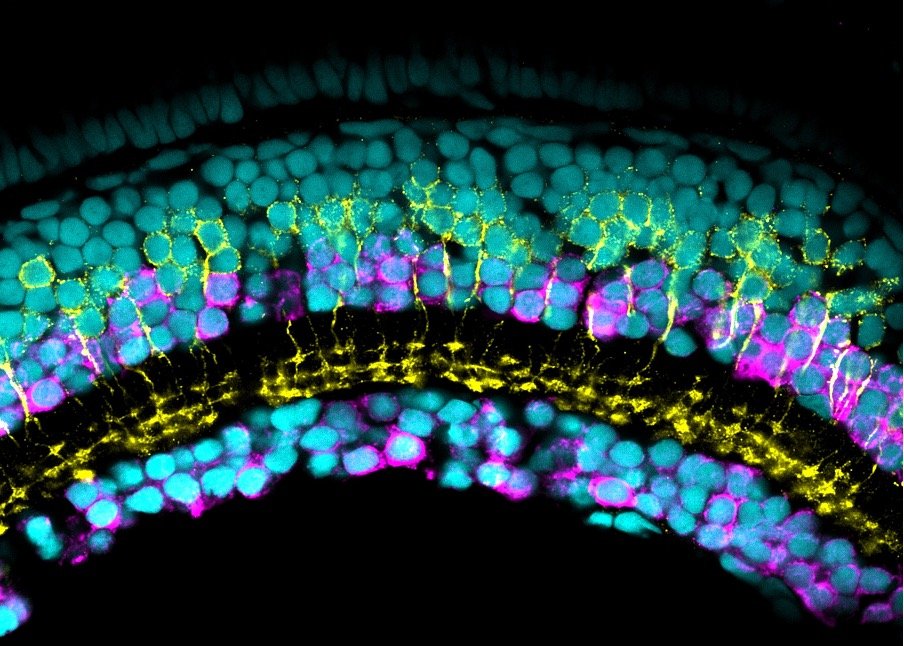

VITAMIN B6 DEPENDENT EPILEPSY

Vitamin B6, normally present in our diet, is critical for brain function. Children with inherited disorders that lead to severe deficiency of B6 suffer from seizures, delayed neurodevelopment and brain malformations.

In collaboration with Prof Philippa Mills (UCL GOS ICH) and Dr Richard Rosch (Imaging Neuroscience) we are trying to better understand the consequences of B6 deficiency on brain function. Using zebrafish disease models that recapitulate the seizure disorders observed in affected children, we will investigate how imbalance of B6 impairs the chemical messengers ('neurotransmitters') in the brain that are required to transmit messages from a nerve cell to a target cell. Thereby, we hope to identify novel therapeutic targets that can be translated into new treatments for affected children to prevent disability and improve children’s quality of life.